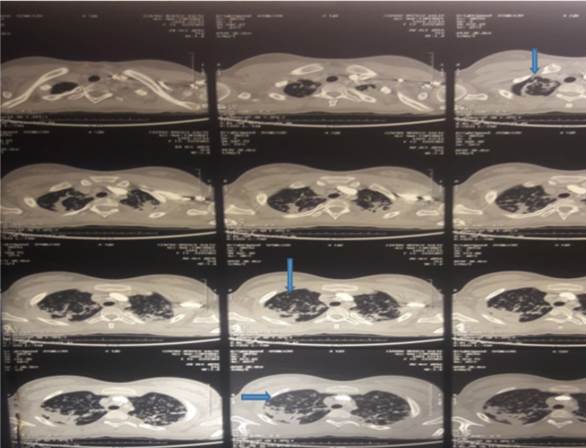

Se solicita tomografía de tórax que evidencian imágenes de cavitación en parénquima pulmonar, consolidación con aspecto de árbol en brote (Figura 3).

Figura 3: Tomografía de tórax que muestra ventana pulmonar. Flechas azules: muestran distintos cortes los cuales se observan imágenes de cavitación del parénquima pulmonar, consolidación, aspecto de árbol en brote.